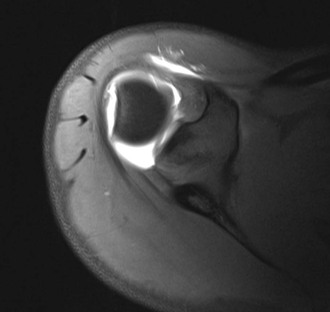

Articulation of the large surface area of the humeral head with the small surface area of the glenoid fossa allows extensive range of motion of the shoulder but also predisposes it to instability. The various soft tissue structures in the area of the shoulder improve joint stability. The glenoid labrum and capsular structures act as static stabilizers, whereas the rotator cuff provides dynamic stabilization of the glenohumeral joint. The glenoid labrum is a thickening of the joint capsule that inserts into the periphery of the osseous glenoid and functions to deepen the shallow glenoid fossa, providing extended coverage of the humeral head.139-141 The superior labrum (Fig. 44-38) is best visualized on coronal MRI and appears as a dark triangular structure extending off of the superior glenoid rim. The anterior and posterior labra (see Fig. 44-36, B) are best seen on axial and coronal images, typically appearing as dark triangular structures; on occasion, however, the normal labrum may appear rounded, blunted, or flattened.140,142 Three glenohumeral ligaments, which represent thickenings of the capsule, also serve to improve stability of the shoulder.

• Sublabral recess—a potential space between the labrum and underlying glenoid that appears as a smooth tapering fluid collection that only partially undermines the superior labrum with no labral displacement (see Fig. 44-36, A)152; a tear differs in that it will show an irregular surface of the labrum with possible labral detachment or displacement (see Fig. 44-40, A)